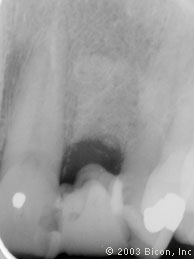

1. | 术前X光片显示失败的根管治疗。 |